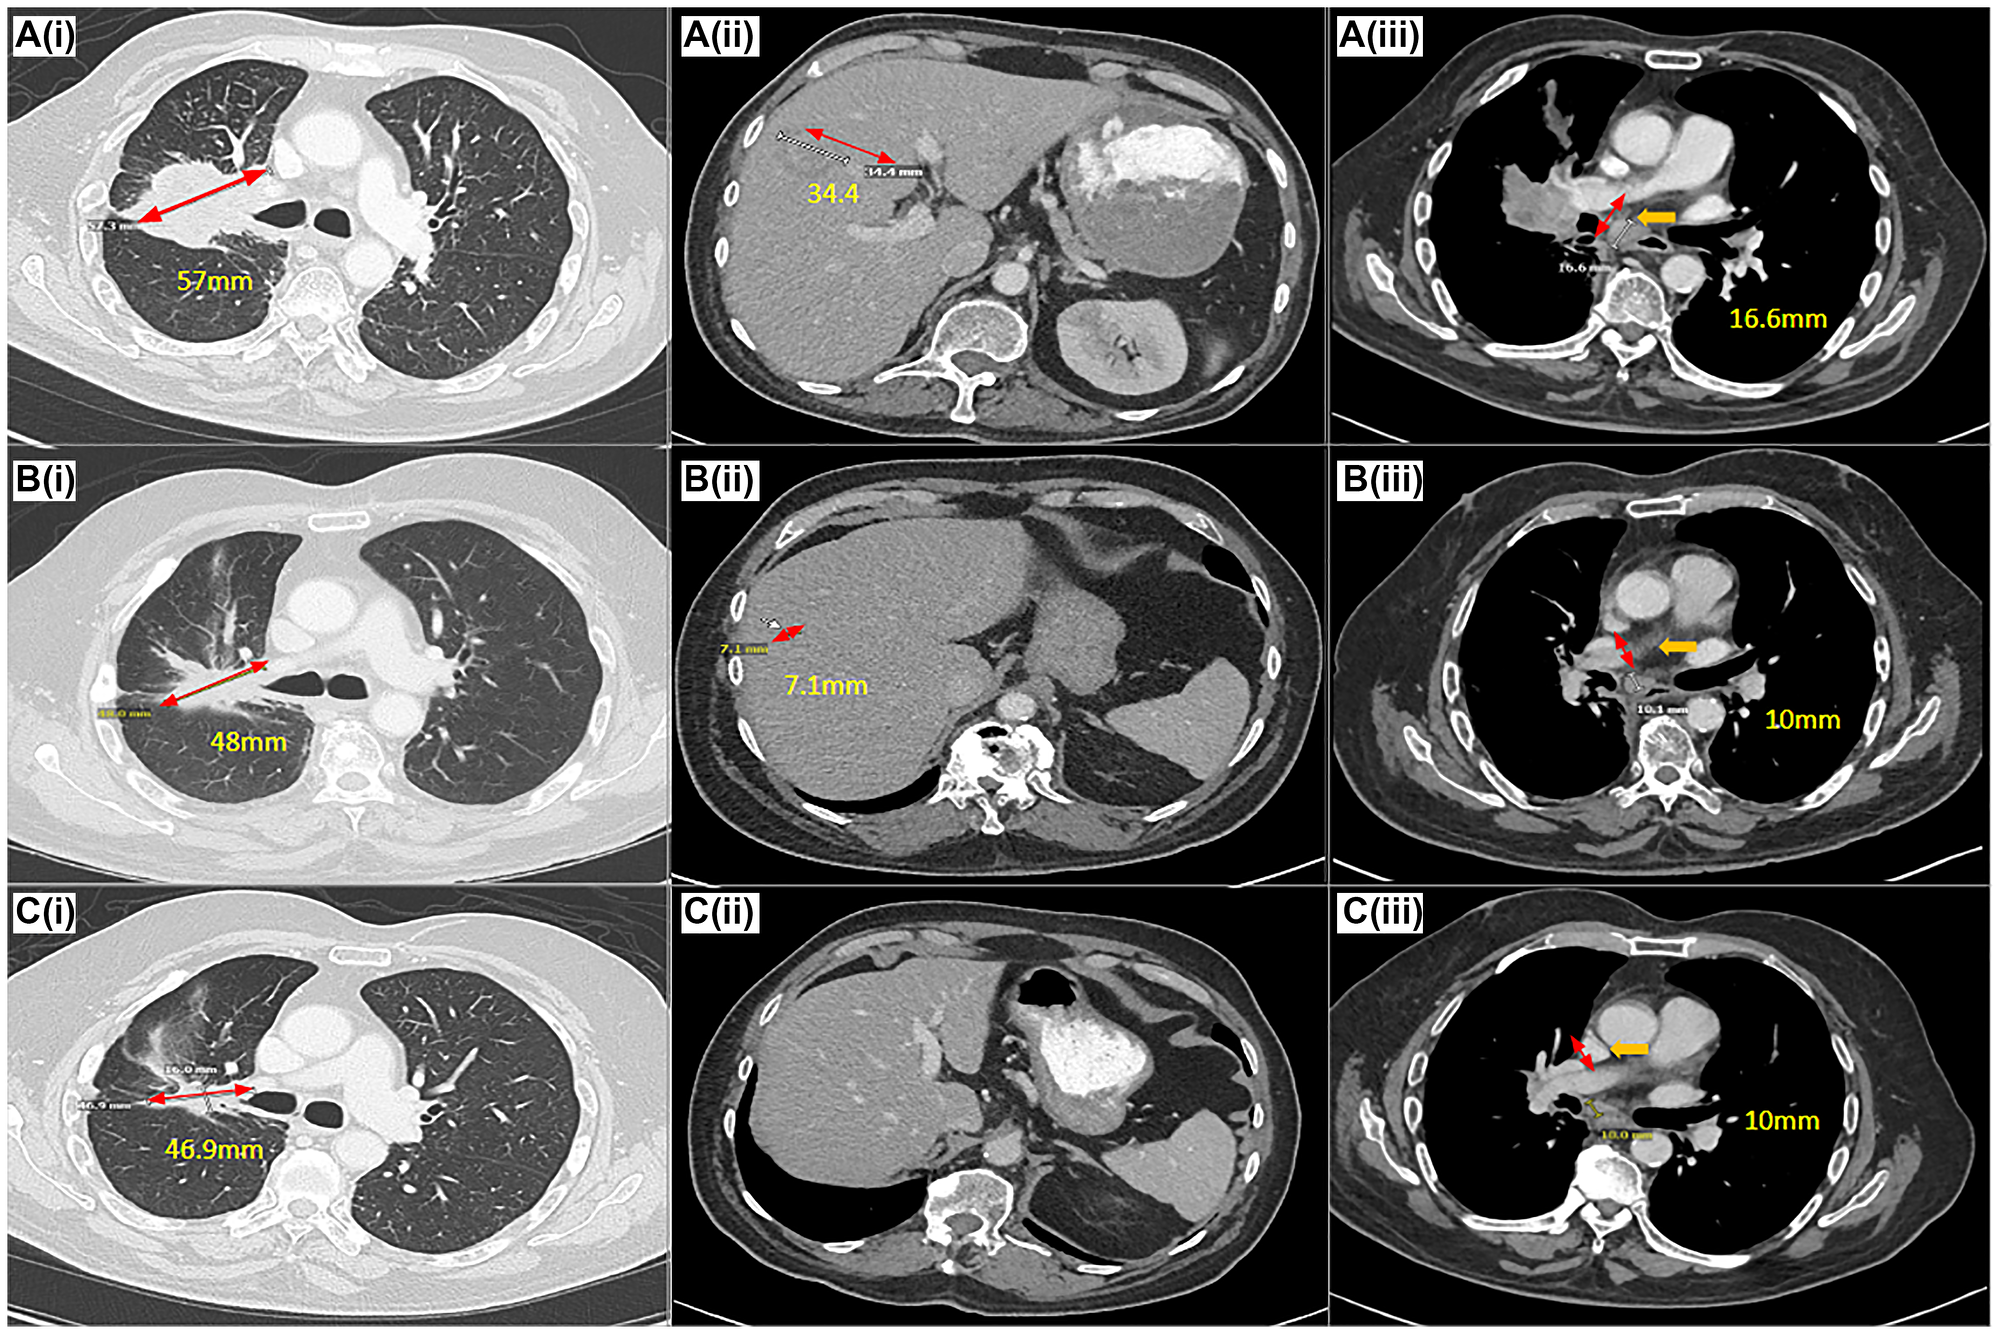

Target response on amivantamab based on RECIST 1.1 on CT scan

Figure 2: Target response on amivantamab based on RECIST 1.1 on CT scan.

CT Chest (i), Abdomen/Pelvis (ii)(iii) at the time of pre-treatment (A), 6 months (B) (complete resolution of CNS disease), 19 months (C) demonstrating a decrease in size of the patient’s lung, liver, mediastinal lesions after treatment with amivantamab. Pre-treatment CT chest with a right upper lobe/perihilar mass, measuring 57 mm in the long axis (A(i)), decreased to 48 mm (B(i)) and 46.9 mm (C(i)) on post-treatment scans. Pre-treatment CT abdomen with a lobular liver lesion, measuring 34.4 mm in the long axis (A(ii)), decreased to 7.1 mm (B(ii)) and complete resolution (C(iii)) on post-treatment scans.